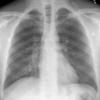

Normal PA Male

Date: 12/06/2014

Views: 6525